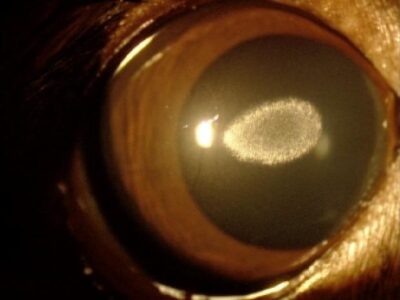

角膜変性症

角膜上皮下にカルシウム沈着

角膜上皮下に脂質やカルシウムが沈着し白い斑点状に見えます。犬種によっては遺伝により、また老齢動物でよく見られます。進行するとその一部が脱落し角膜潰瘍をおこすことがあります。